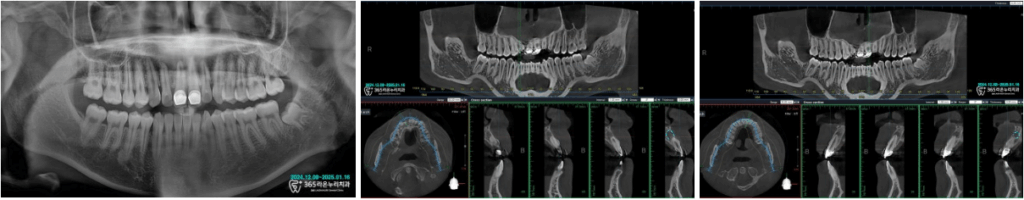

오산역 치과 에서는

엑스레이 및 CT를 촬영한 이후,

치아 뿌리 끝에 염증이 어느정도로

퍼졌는지 확인을 거쳤습니다.

검사 결과 치아 뿌리 끝까지 염증이 꽤 퍼졌지만

치아를 뽑지 않고 보존할 수 있게

신경치료 및 재보철 치료 진단을 내렸습니다.